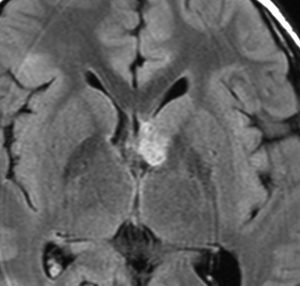

10歳の時に水頭症による頭痛と嘔吐で発症しました。結節性硬化症に合併したSEGAです。生検術,内視鏡手術,開頭術を受けて腫瘍を小さくして,その後にエベロリムスの投与を受けていました。これはエベロリムス投与後の画像です。この腫瘍にさらにエベロリムスの投与を続けるかという疑問があります。やめれば再燃することが多いからです。

結論として,これは完全摘出できるので摘出した方がいいです。なぜならそれでこの腫瘍は治癒するからです。右のFLAIR画像で見られるように発生部位となる尾状核のところでは一見,脳組織との境界が不明瞭にみえるのですが,腫瘍はある程度の硬さがあるので脳組織との区別をすることができて,完全摘出できるものです。